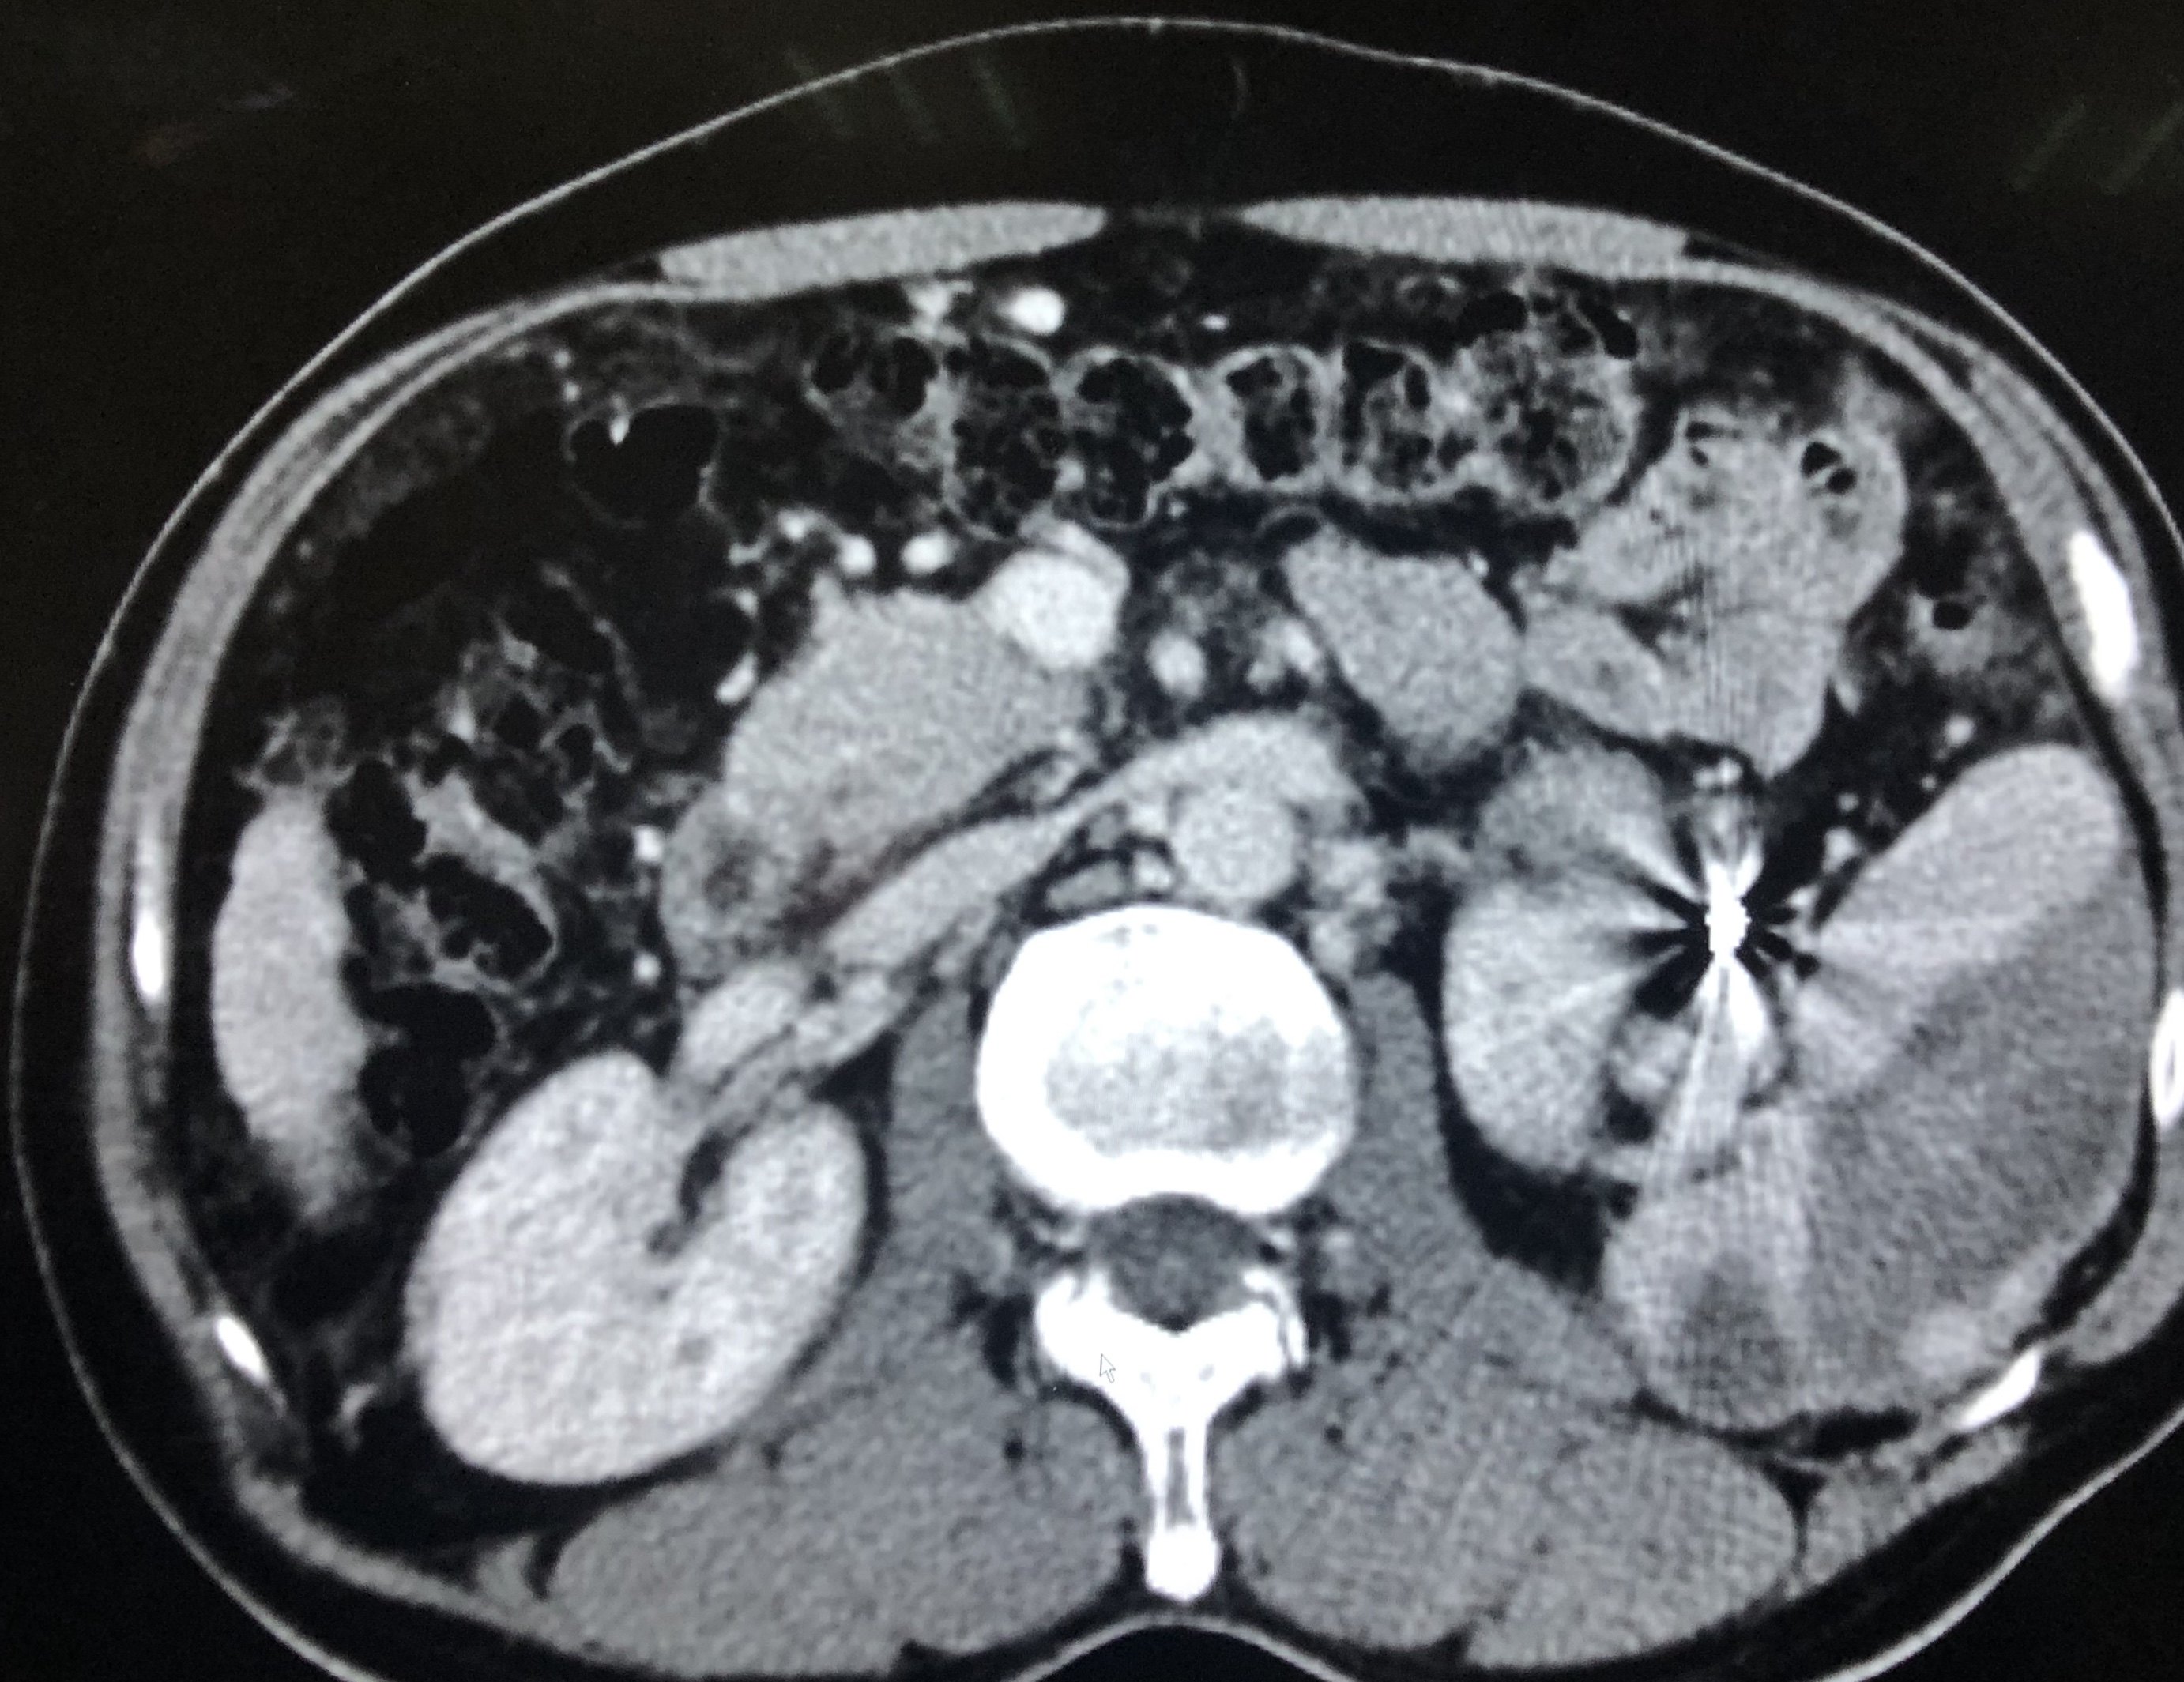

行脾脏多点消融治疗,以15g微波消融针穿刺脾脏,并进行大功率多位点消融治疗。

行脾脏多点消融治疗,以15g微波消融针穿

刺脾脏,并进行大功率多位点消融治疗。